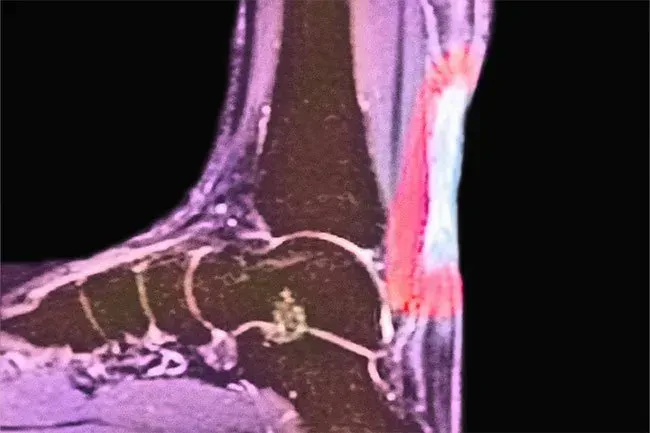

Tendinite d'Achille

L'Achille est le tendon que vous utilisez pour fléchir votre pied lorsque vous montez des escaliers ou montez sur vos orteils. L'âge et l'approvisionnement en sang réduit peuvent affaiblir le tendon. Votre talon ou le dos de votre cheville peut blesser. Le glaçage et les médicaments peuvent aider à lutter contre le gonflement. N'ignorez pas le problème. Vous pourriez avoir besoin d'une intervention chirurgicale pour de graves larmes.